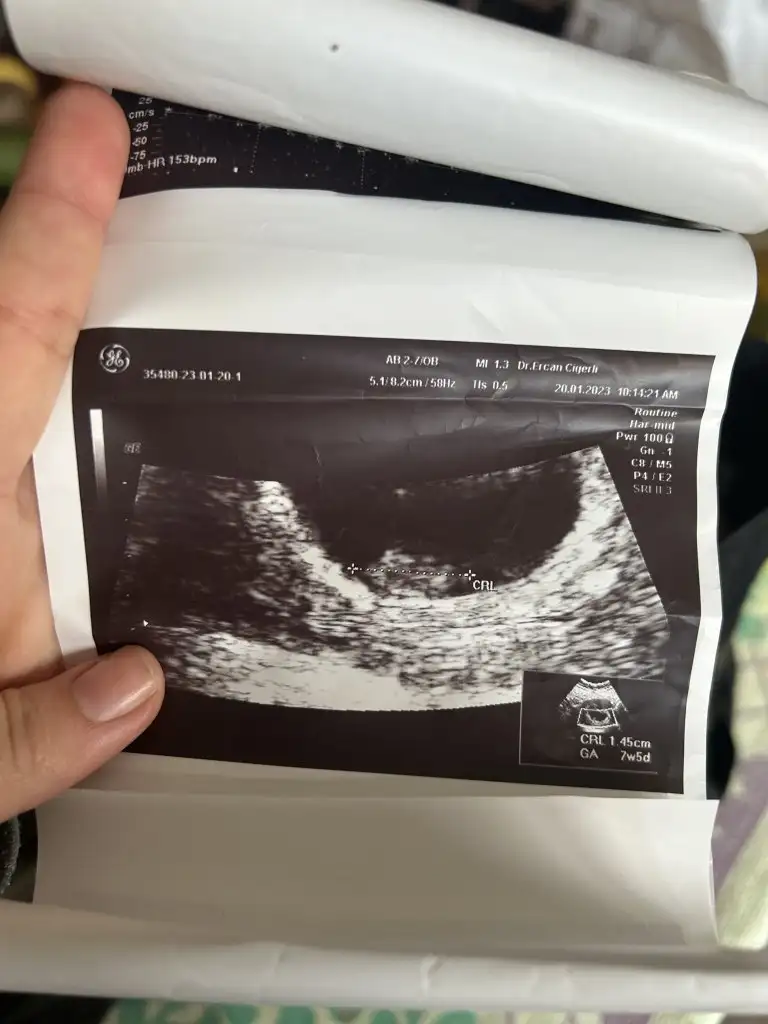

Pekiii bende ne dersin ?

Üstteki 9 haftalik diger ikisi 7 haftalik, ve vaginal ultrason :)